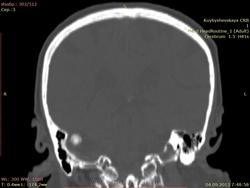

дополнительное образование высокой плотности справа. подскажите

пациентка жалуется на головные боли, больше справа. Подскажите что это за образование справа? первый раз вижу. и деструкции стенки вроде бы нет. плотность высокая.

Остема или небольшая обызвествленная менингиома, что почти одно и тоже. Да менингиому на первое место надо было поставить :)

По-моему обызвествлённая менингиома.

+1. Менингиома.

Стандартное место для менингиомы

Ага, задней грани пирамиды, как некоторые пишут.